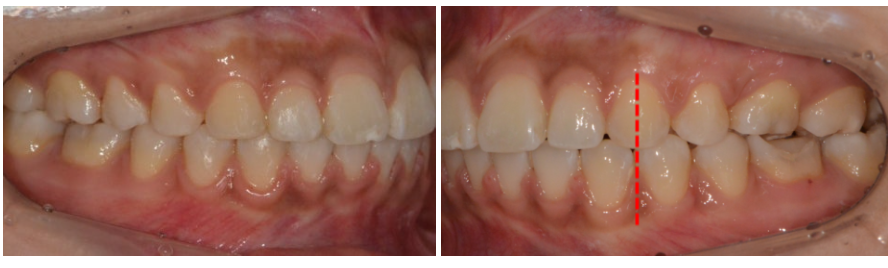

상하악 치열 중심선 비대칭

상악 전치 돌출, 하악 전치 각도 양호

좌측 어금니 교합 어긋남, 우측 비교적 안정적

상하악 치열의 중심선 일치

좌측 어금니 교합 안정화

상악 전치 돌출감 자연스럽게 개선

최소 발치로 치열 대칭과 자연스러운 옆모습 달성